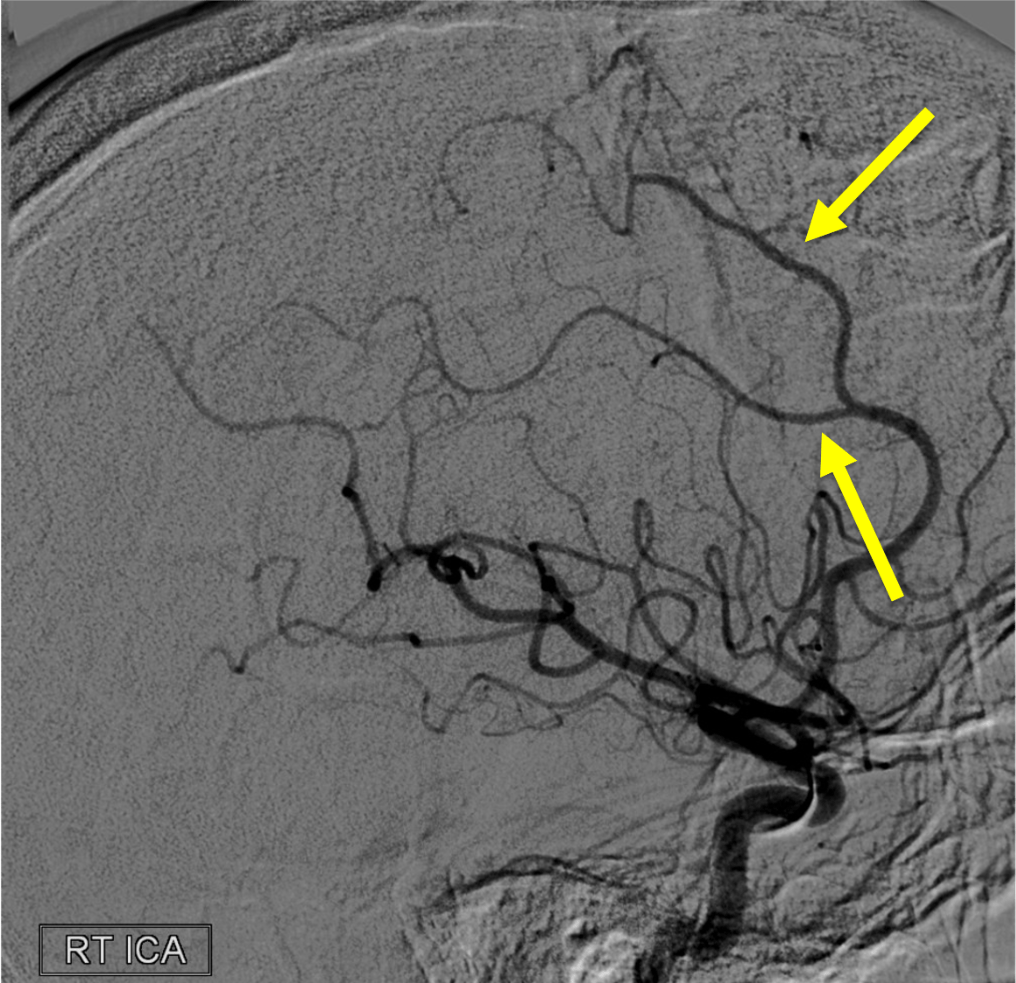

On this lateral view R ICA injection, name these two branches:

Pericallosal and callosomarginal arteries off the ACA